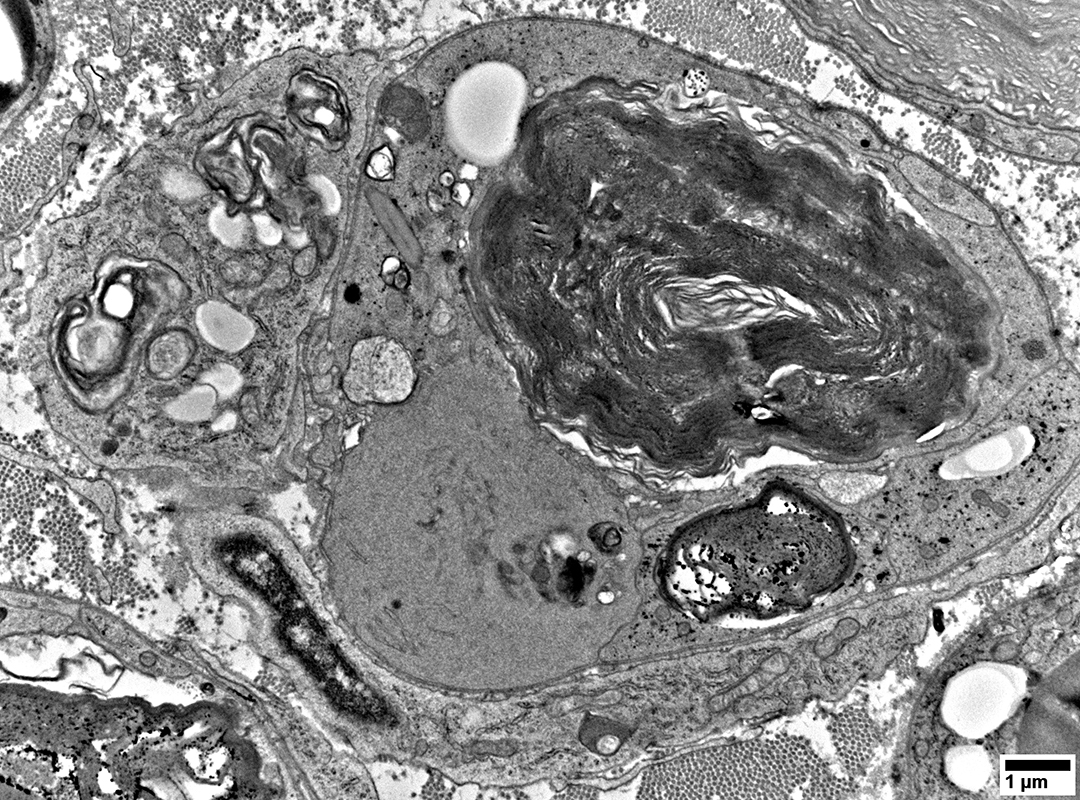

Lipid Droplets & Myelin debris segregated in different Schwann cell processes

From: R Schmidt